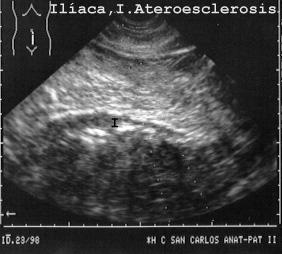

La Fig 23 muestra una arteria ilíaca con arteriosclerosis,

23ILIACA.JPG (30814 bytes)

Fig 23